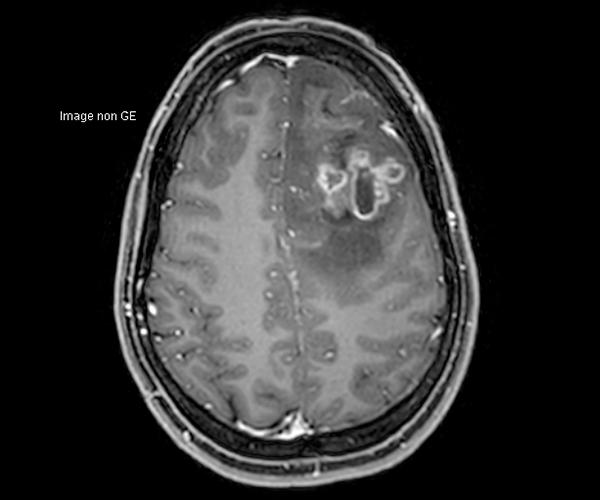

L’amélioration de la résolution spatiale s’applique à l’exploration morphologique des hippocampes dans le diagnostic de la maladie d’Alzheimer, à la détection de petites lésions de sclérose en plaques ou de métastases, à l’étude fine du cortex dans les épilepsies.

L’augmentation de l’effet de susceptibilité magnétique à plus haut champ permet d’améliorer la détection des hémorragies et est utilisé également dans l’imagerie de perfusion (tumeurs) et l’IRM fonctionnelle (BOLD). L’allongement du T1 à plus haut champ entraîne une meilleure saturation des tissus statiques et par conséquent une augmentation du contraste sang/tissus dans l’AngioIRM.